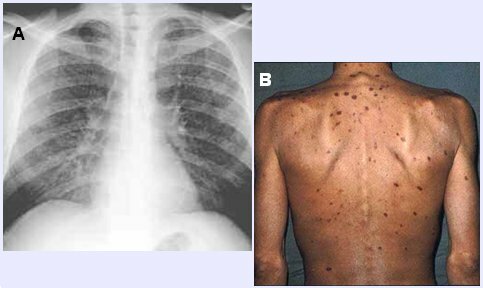

La CDC en EE.UU describe 5 nuevos casos de neumonía ocasionados por Pneumocystis carinii y varios casos de Sarcoma de Kaposi en personas jóvenes gay previamente sanos en la ciudad de los Angeles.